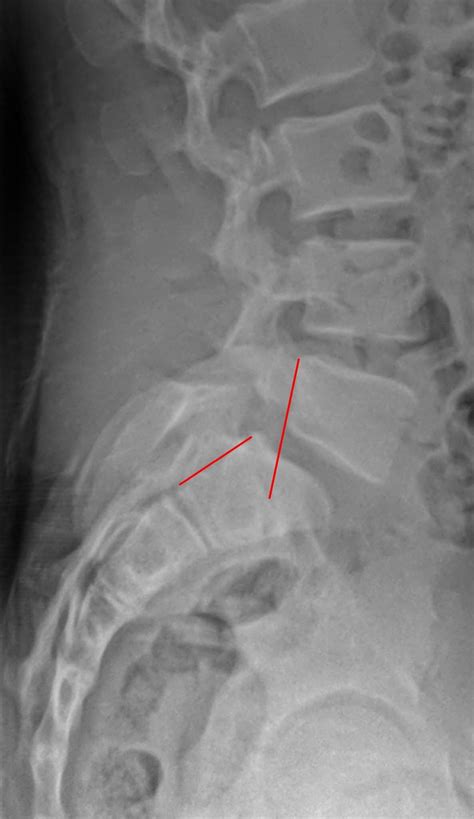

Spondylolisthesis Grade 1 is characterized by a slight forward slip of one vertebra over the one below it, typically less than 25% of the vertebral body. This condition can occur in various parts of the spine but is most commonly found in the lumbar region, particularly at the L5-S1 level. The slip can be caused by several factors, including degenerative changes, trauma, or congenital abnormalities.

• Spondylolysis: A defect or fracture in the pars interarticularis, a small bone in the spine, can lead to spondylolisthesis.

• Imaging Tests: X-rays, CT scans, and MRI scans are commonly used to visualize the spine and determine the degree of slippage.

Imaging tests are particularly important for confirming the diagnosis and assessing the severity of the condition. X-rays can show the alignment of the vertebrae, while CT scans and MRI scans provide detailed images of the soft tissues and nerves.